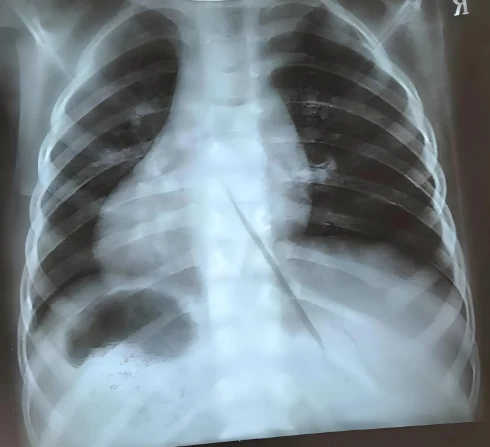

患者报告的主诉包括发热1天余,最高体温达38.9度,同时伴有呼吸道症状,如咳嗽和咳痰,后检测新冠抗原呈阳性,但未未见明显的慢性疾病史和药物过敏史。这些症状以及检查结果均指向急性感染,特别是支气管的急性炎症。

支气管是连接气管和肺泡的管道,当感染入侵时,支气管内壁的黏膜会出现炎症反应,导致黏液分泌增加,气道变得狭窄。这不仅会引起咳嗽、痰多等症状,还可能出现胸闷、呼吸不畅的情况。在病程初期,感冒或流感的症状比较常见,但若不及时处理,可能会导致更严重的并发症。